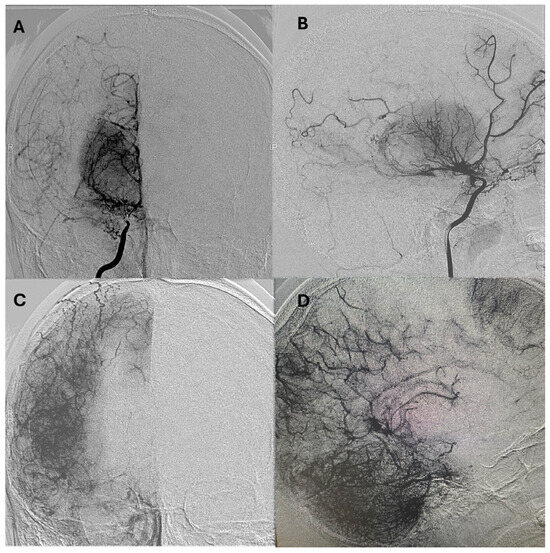

Representative postoperative angiographic images are shown in Figure 1, Figure 2 and Figure 3. The mean operative time was 3.2 h and the average length of hospital stay was 7 days. All patients were monitored in the pediatric intensive care unit for 24–48 h before being transferred to the ward.

Figure 3. Postoperative anteroposterior DSA in a pediatric patient with Moyamoya disease, demonstrating successful indirect revascularization via encephaloduroarteriosynangiosis (EDAS). There is marked neovascularization originating from the superficial temporal artery, along with reduced opacification of the internal carotid arteries. (A) Left vertebral artery; (B) right internal carotid artery; (C) left internal carotid artery; (D) right external carotid artery; (E) left external carotid artery. DSA: digital subtraction angiography; EDAS: encephaloduroarteriosynangiosis.